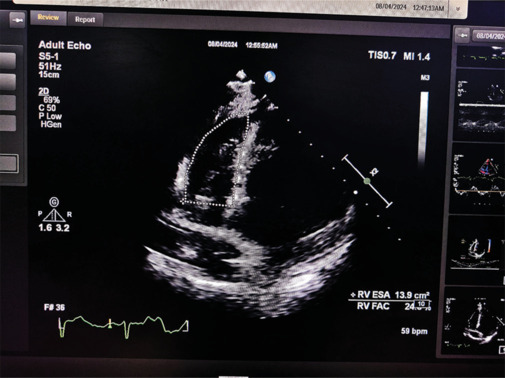

Materials and methods: A prospective study of 100 HF patients categorized into HFpEF (left ventricular EF [LVEF] >50%, n = 16), HFmrEF (LVEF 40%-50%, n = 47), and HFrEF (LVEF < 40%, n = 37). Echocardiographic assessments, including RV GLS, were performed using a standardized protocol on the Philips EPIC 7C system. RV GLS was analyzed as a sensitive marker for poor outcomes, defined by major adverse cardiac events (MACE) and worsening functional status.

Results: RV GLS demonstrated significant variation among the groups. Patients in Group C (HFrEF, LVEF < 40%) exhibited markedly lower RV GLS compared to Group A (HFpEF, LVEF > 50%) (-13.5 ± 5.24 vs. -16.8 ± 4.21; P = 0.006). In addition, a significant difference was noted between Group C and Group B (HFmrEF, LVEF 40-50%) (-13.5 ± 5.24 vs. -14.6 ± 4.15; P = 0.047). The predictive value of RV GLS for poor outcomes in HF patients was supported by a sensitivity of 75% and specificity of 69.12%, with a cutoff threshold of - 14.7%.

Conclusions: RV GLS serves as a dependable marker for predicting poor outcomes in HF patients, with a defined cutoff value of -14.7%. This metric holds substantial clinical promise for effective risk stratification and timely intervention, demonstrating a sensitivity of 75% and a specificity of 69.12%.